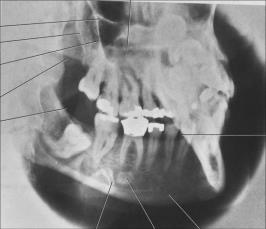

Lateral jaw: body of mandible

use for a lateral jaw: body of mandible

to evaluate impacted teeth, fractures, and lesions located in the body of the mandible

Lateral jaw: body of the mandible is ideal for

children, patients with limited jaw opening due to: Trauma, swelling or infection